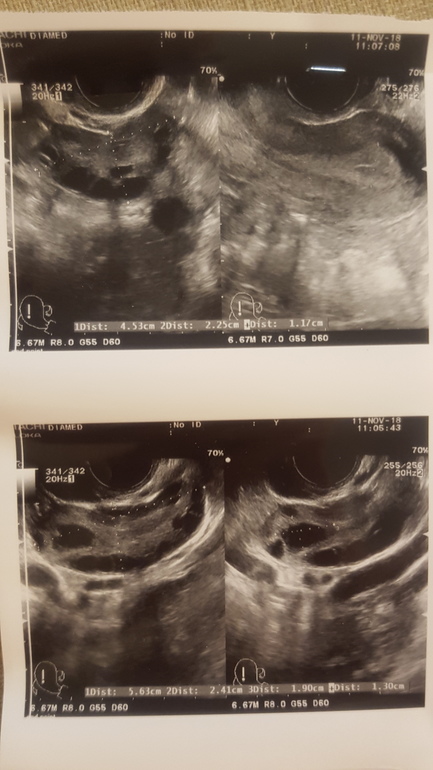

В июле было прерывание анэмбрионии таблетками, без чистки, все ок, потом пропала О на 3 цикла подряд (подтверждено УЗИ отсутствие О), этот цикл 4ый - делала тесты на О- полосатились жирно 3 дня (О у меня всегда на 18-23 ДЦ), сегодня на 20 ДЦ сделала УЗИ, на котором как сказала врач картина спорная, а именно - обнаружена жидкость в позадиматочном пространстве (как-будто О была вчера) и обнаружено желтое тело с формой как-будто О была НЕСКОЛЬКО дней назад.

Узист сказала, что непонятно- когда была О и была ли вообще...

Вот я также делала фолликулометрию, и тоже в конце так и не поняла отврача была овуляция или нет... Все так же спорно, как и с тестами. Но эндик, то у вас отличный. Наличие жидкости и жёлтое тело вроде как наоборот подтверждают, что овуляция была. Только вот когда....

Я вообще не понимаю по УЗИ чем отличается фолликулы от ЖТ, одинаковые темные кружочки, только размеры разные...

Какие там контуры? Фиг поймешь... 🤯🧐

Вот теперь и гадай, было или не было О....